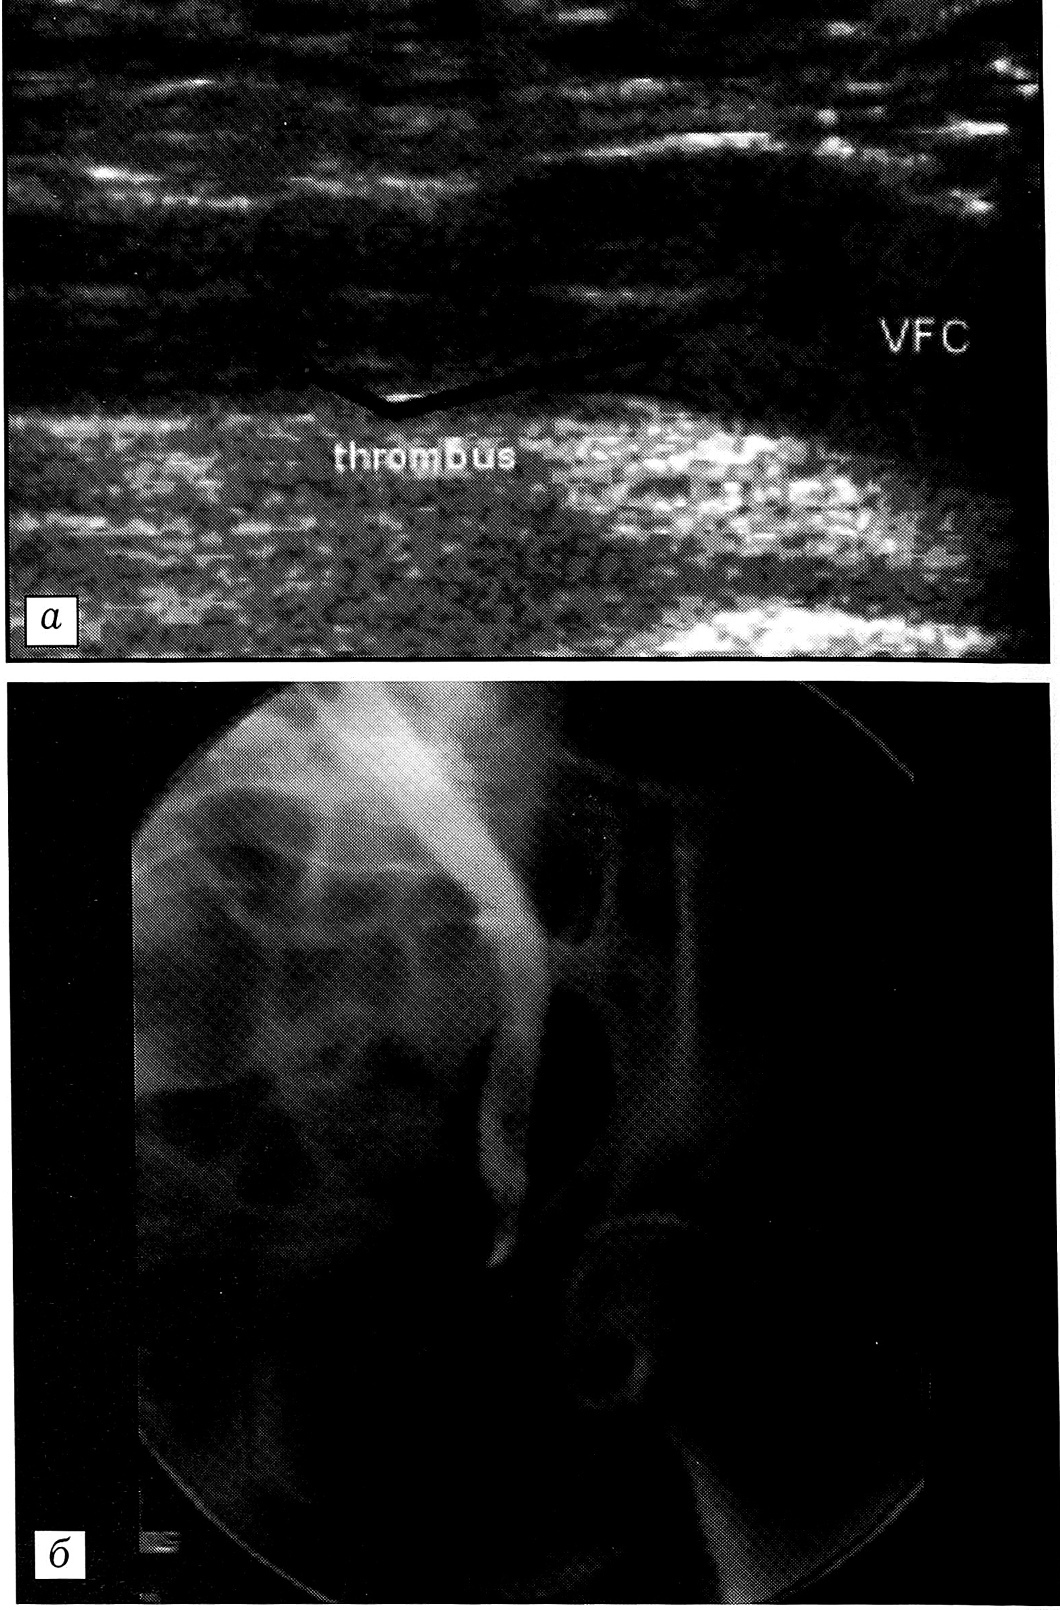

До операции лишь у одной пациентки был выявлен флотирующий тромб с локализацией верхней границы под створками проксимального клапана поверхностной бедренной вены. Больная поступила в стационар на 7-е сутки после перелома шейки бедренной кости. В день поступления при УЗ-ангиосканировании диагностирован ТГВ травмированной конечности (рис. 1, а). При выполнении ретроградной илиокаваграфии подтверждены как само наличие ТГВ, так и локализация его верхней границы (рис. 1, б). Процедура завершена установкой кава-фильтра.

Рис. 1. Ультрасонограмма (а) и флебограмма (б) больной с переломом шейки бедра до операции эндопротезирования. На ультрасонограмме: флотирующий тромб (черные стрелки) в поверхностной бедренной вене с верхушкой под створками проксимального клапана (белые стрелки).